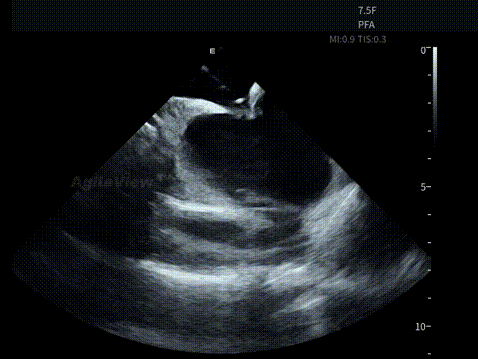

▶【消融阶段:PFA预设模式,贴靠状态可视,判断更直接】

进入消融阶段后,AgileView™ ICE 持续提供近场实时影像,动态显示消融导管与心房组织之间的空间关系与贴靠状态。在肺静脉隔离过程中,ICE 下可清晰观察到导管在左上、左下、右上及右下肺静脉口部的贴靠情况,为能量释放位置的确认提供直接影像依据。

PulseSelect™导管贴靠-LSPV

PulseSelect™导管贴靠-LIPV

PulseSelect™导管贴靠-RSPV

PulseSelect™导管贴靠-RIPV

在完成四根肺静脉口部及前庭消融后,术者使用PulseSelect™导管进行上腔静脉消融,ICE 同样用于评估导管送鞘及贴靠状态,使关键步骤始终建立在清晰可见的影像反馈之上。

PulseSelect™导管贴靠-SVC

在冷冻消融手术中,ICE 亦用于辅助评估冷冻球囊导管在肺静脉口部的封堵状态与空间位置,确保导管贴靠及消融有效性。

AFA Pro冷冻球囊封堵